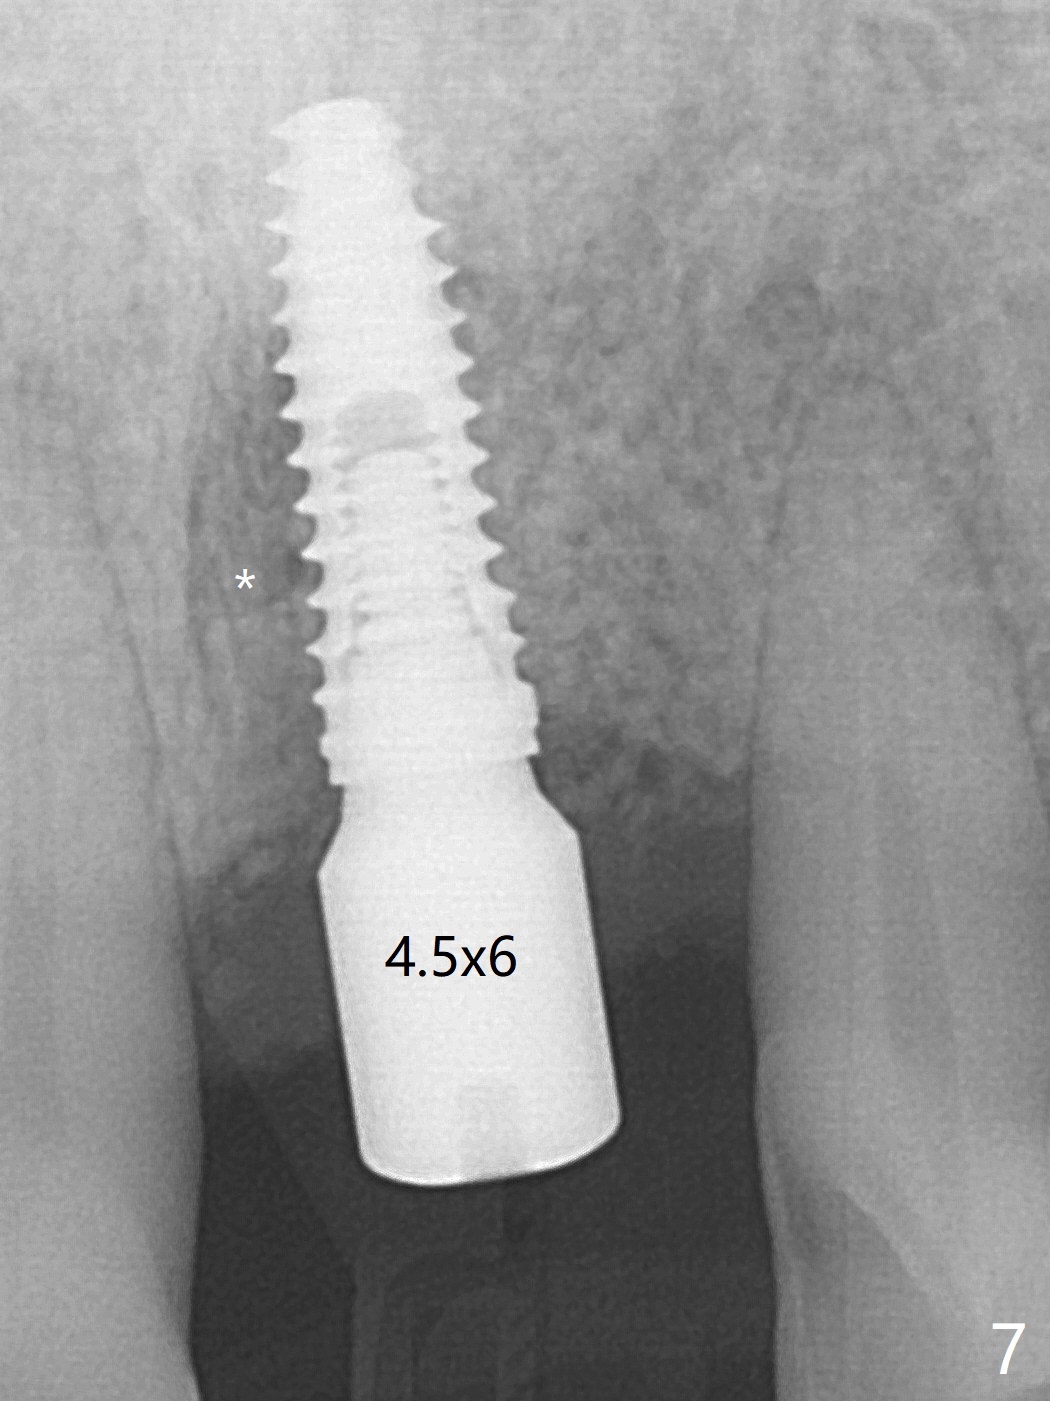

左上1(图一)拔除,植骨,使用带钛架不可吸收膜(图二)后十个月准备植牙(图三),在没有术中根尖片指导下(导板习惯),在牙槽嵴正中开始钻洞,第一个钻头最后一两个毫米觉得有突破感,但是颊侧舌侧没有穿孔,然后植入3.5x11.5毫米植体(图五,扭力>35 Ncm),术后射线表明植体接近切牙管(图四:*)。考虑到病人要离城,颊侧第一螺纹暴露(图六),舌侧骨板薄(图五),植骨,放置愈合基台(图七)。 术后十一天CT显示植体没有侵犯切牙管(图八:I);植体颊侧骨粉(箭头)似乎可以解释颊侧饱满(图九)。第二原因是减张缝合,胶原膜暴露(*),而下面骨粉没有暴露,以后伤口应该是二期愈合。